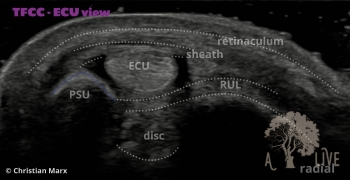

carpal ligaments